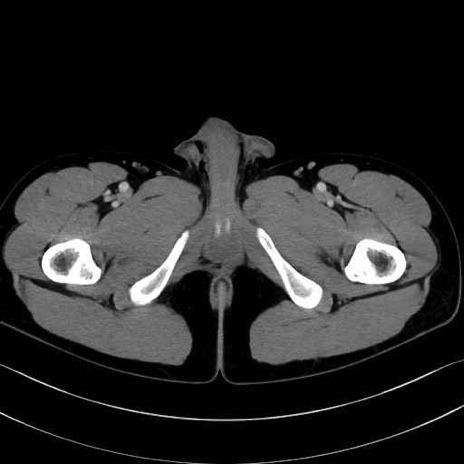

梨状筋(piriformis muscle) のCT画像の解剖

梨状筋 (Piriformis)

内閉鎖筋 (Obturator internus)

外閉鎖筋 (Obturator externus)

大腿方形筋 (Quadratus femoris)